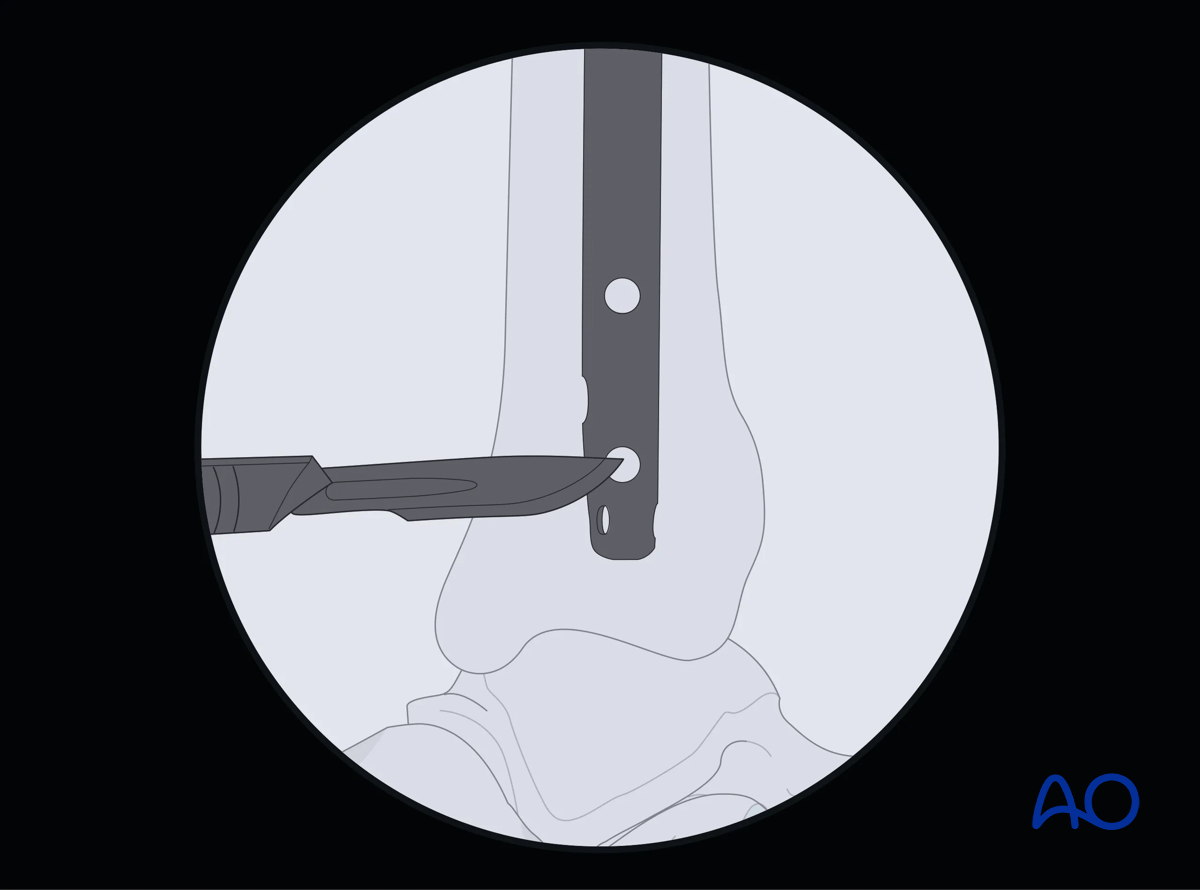

The central ray of the fluoroscope must pass through the locking hole so that its image is perfectly round and centered on the display screen. This confirms that the central ray is perpendicular to the nail.

Suprapatellar intramedullary nailing, Distal interlocking with fluoroscopic guidance

Drill tip positioning

The drill tip is positioned over the center of the locking hole.

Alignment and drilling

The drill tip must be aligned with the fluoroscopic central ray. The drill is then advanced through the near tibial cortex, the locking hole in the nail, and the far tibial cortex. Its position is confirmed radiographically. If correct, screw length is measured, the appropriate screw is inserted, and its proper placement is confirmed radiographically.